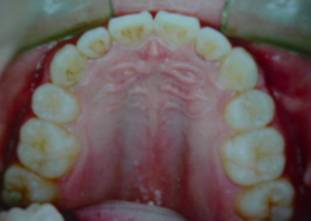

答二、拔牙以后的牙缝在矫治器的作用下,是完全可以关闭的。

一般来说,拔牙以后的牙缝可以被两个方面的牙齿移动所关闭,一个是前面不齐、前突的牙齿向拔牙间隙移动,占据部分拔牙间隙,还有就是后面的大牙也可以向关(拔牙间隙)移动,这样就可以关闭了这个间隙。

拔牙的目的是为了给前突、拥挤的牙齿提供足够的间隙,另外还用于调整牙齿的咬合关系。所以问题是:你牙齿间的这些可以用的空隙有多少?如果多,那就好办,不拔牙可以;如果少,那还是有可能要拔牙。